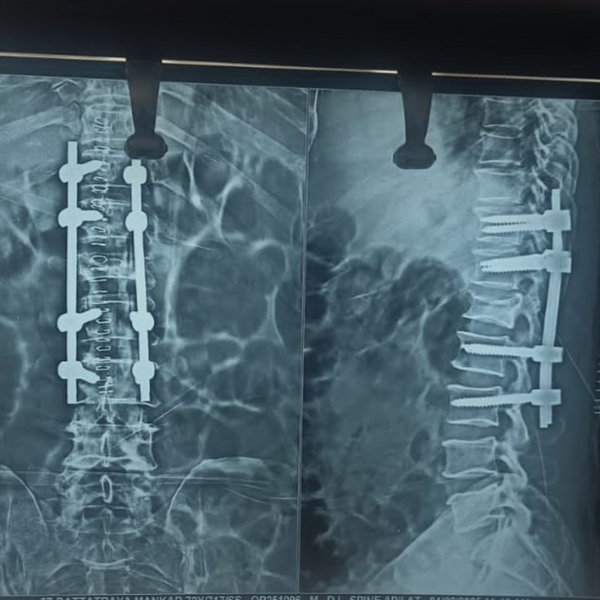

Cervical Disc Prolapse Treatment

Cervical Disc Prolapse Advanced Cervical Spine Care by Dr. Nitish Agrawal – Best Spine Surgeon in Pune Cervical Disc Prolapse, commonly known as slip disc in the neck, occurs when a disc in the cervical spine bulges or herniates and compresses nearby nerve roots or the spinal cord. This condition…